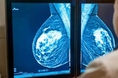

호치민시 유방암 환자 20년 새 70% 증가…조기 발견율은 26%에 불과

[굿모닝베트남] 베트남 최대 도시인 호치민시에서 유방암 환자가 급증하고 있지만 조기 발견율은 여전히 낮아 우려가 커지고 있다. 최근 발표에 따르면 1995년부터 2015년까지 20년 사이 호치민시의 유방암 환자 수는 약 70% 증가했으며, 조기에 발견되는 비율은 26%에 그친 것으로 나타났다. 이 같은 내용은 웬디 Y. 첸 부교수가 3월 14일 호치민시 남사이공 국제종합병원에서 열린 ‘암 치료 및 관리의 최신 발전’ 학술대회에서 발표했다. 세계 암 통계 자료를 제공하는세계암기구(GLOBOCAN) 자료에 따르면 유방암은 현재 베트남 여성 암 환자의 약 29%를 차지하고 있으며 매년 약 2만5천 건의 신규 환자가 발생하고 있다. 이로 인해 유방암은 간암을 넘어 베트남에서 가장 흔한 여성 암으로 자리 잡았다. 특히 전문가들은 발병 연령이 점차 낮아지는 추세를 보이고 있다는 점을 우려하고 있다. 이는 조기 검진에 대한 인식 부족과 의료 접근성 문제 등 여러 요인이 복합적으로 작용한 결과로 분석된다. 웬디 첸 교수는 동남아시아 국가들의 유방암 발병률은 서구 국가들보다 낮지만 사망률은 오히려 더 높다고 설명했다. 가장 큰 이유는 정기 검진 시스템이 충분히 확산되지 않았